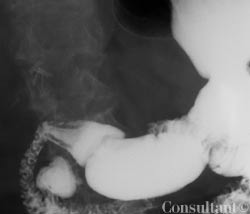

Excessive belching, abdominal bloating, and flatulence caused an 89-year-old woman to seek medical attention. She reported that these previously mild and intermittent symptoms of 20 years’ duration had worsened during the last 2 years.